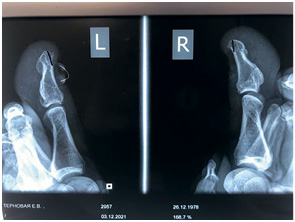

Иллюстрация к книге — Подология понятно. Важен каждый шаг. Справочник по проблемам подологии для клиентов и мастеров эстетики [i_273.jpg]

На этом снимке отчетливо виден экзостоз

Иллюстрация к книге — Подология понятно. Важен каждый шаг. Справочник по проблемам подологии для клиентов и мастеров эстетики [i_274.jpg]

Иллюстрация к книге — Подология понятно. Важен каждый шаг. Справочник по проблемам подологии для клиентов и мастеров эстетики [i_275.jpg]

Иллюстрация к книге — Подология понятно. Важен каждый шаг. Справочник по проблемам подологии для клиентов и мастеров эстетики [i_276.jpg]

Клиент обратился с проблемой отрастания здорового ногтя, был отправлен на консультацию к хирургу на предмет экзостоза. Диагноз подтвердился, была проведена операция, и спустя месяц клиент обратился к нам за помощью в отращивании здоровой ногтевой пластины